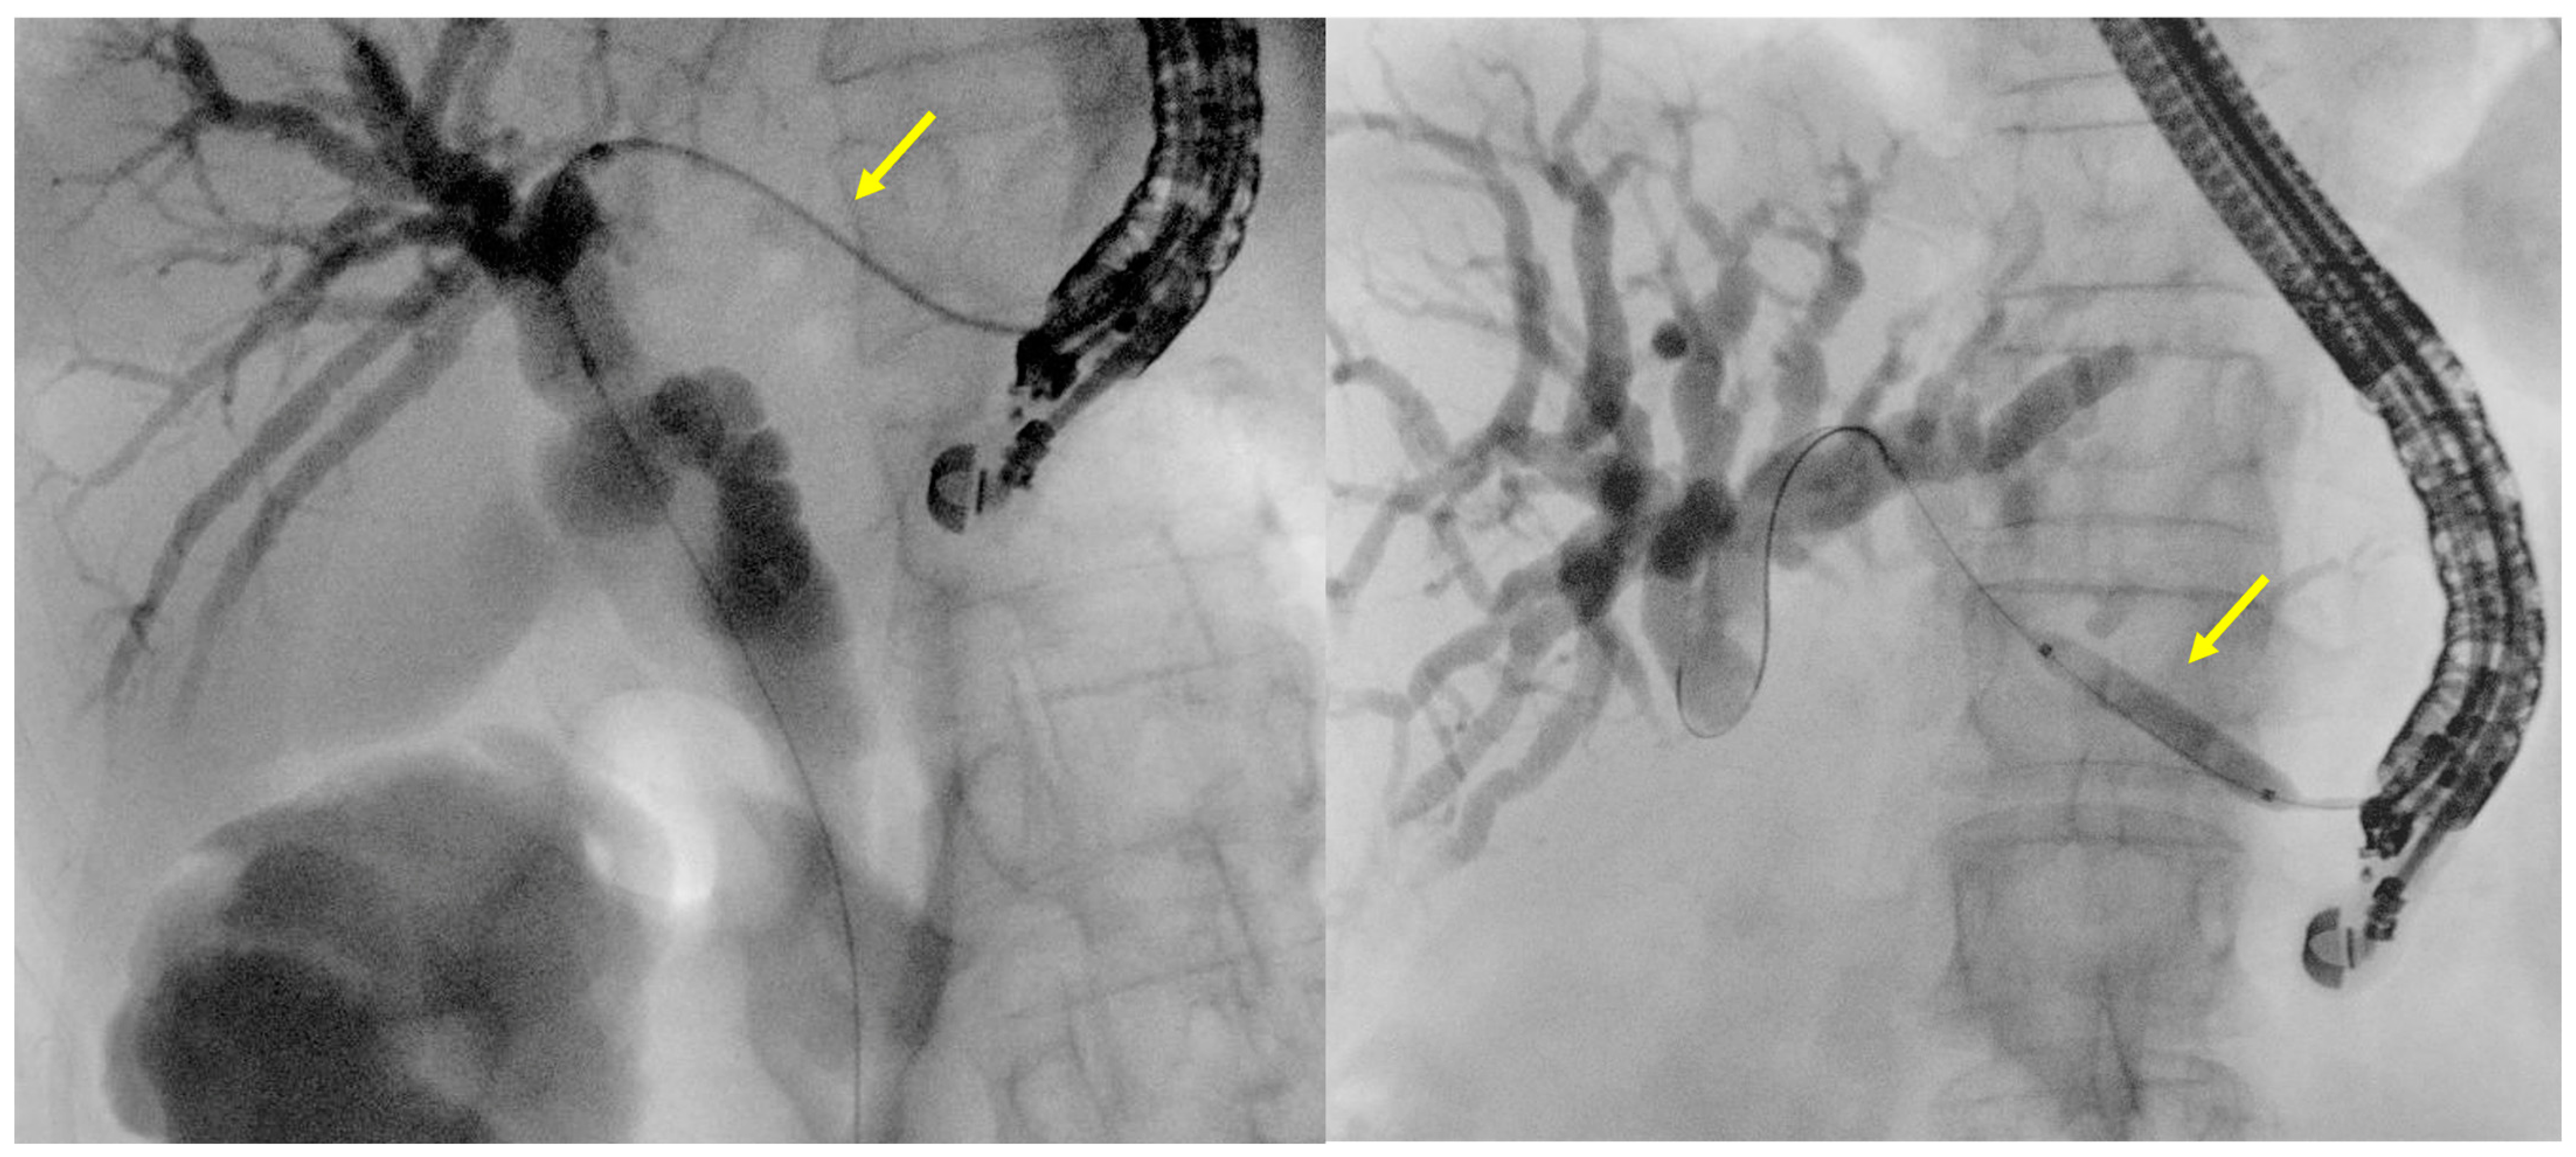

- Intrahepatic bile duct puncture

- Fluoroscopy and guidewire manipulation into the biliary tree